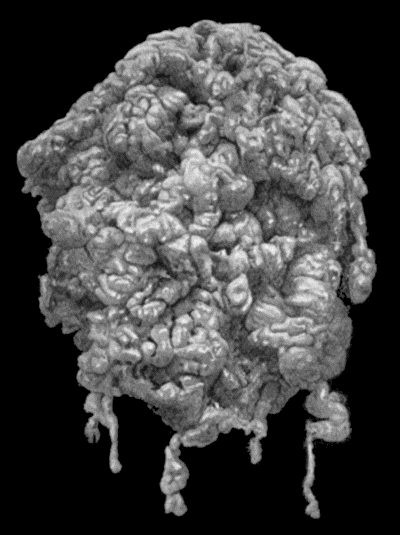

335 80.Chronic Hodgkin's Disease in boy æt. 11

337 81.Lymphadenoma in a woman æt. 44

338 82.Lympho Sarcoma removed from Groin